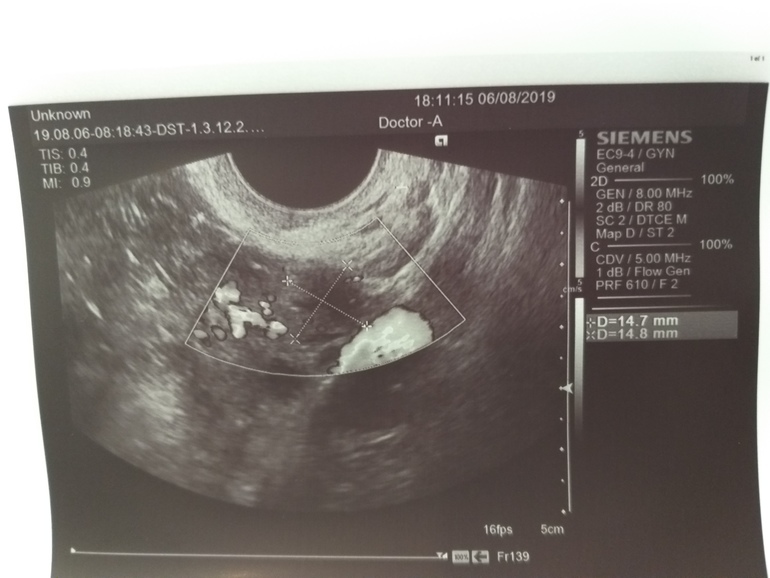

По словам врача много свободной жидкости и она везде, плюс какое-то расширение (какое и чего непонятно, в заключении про это ничего не сказано), врач говорит что это указывает на воспаление, эндометрит.